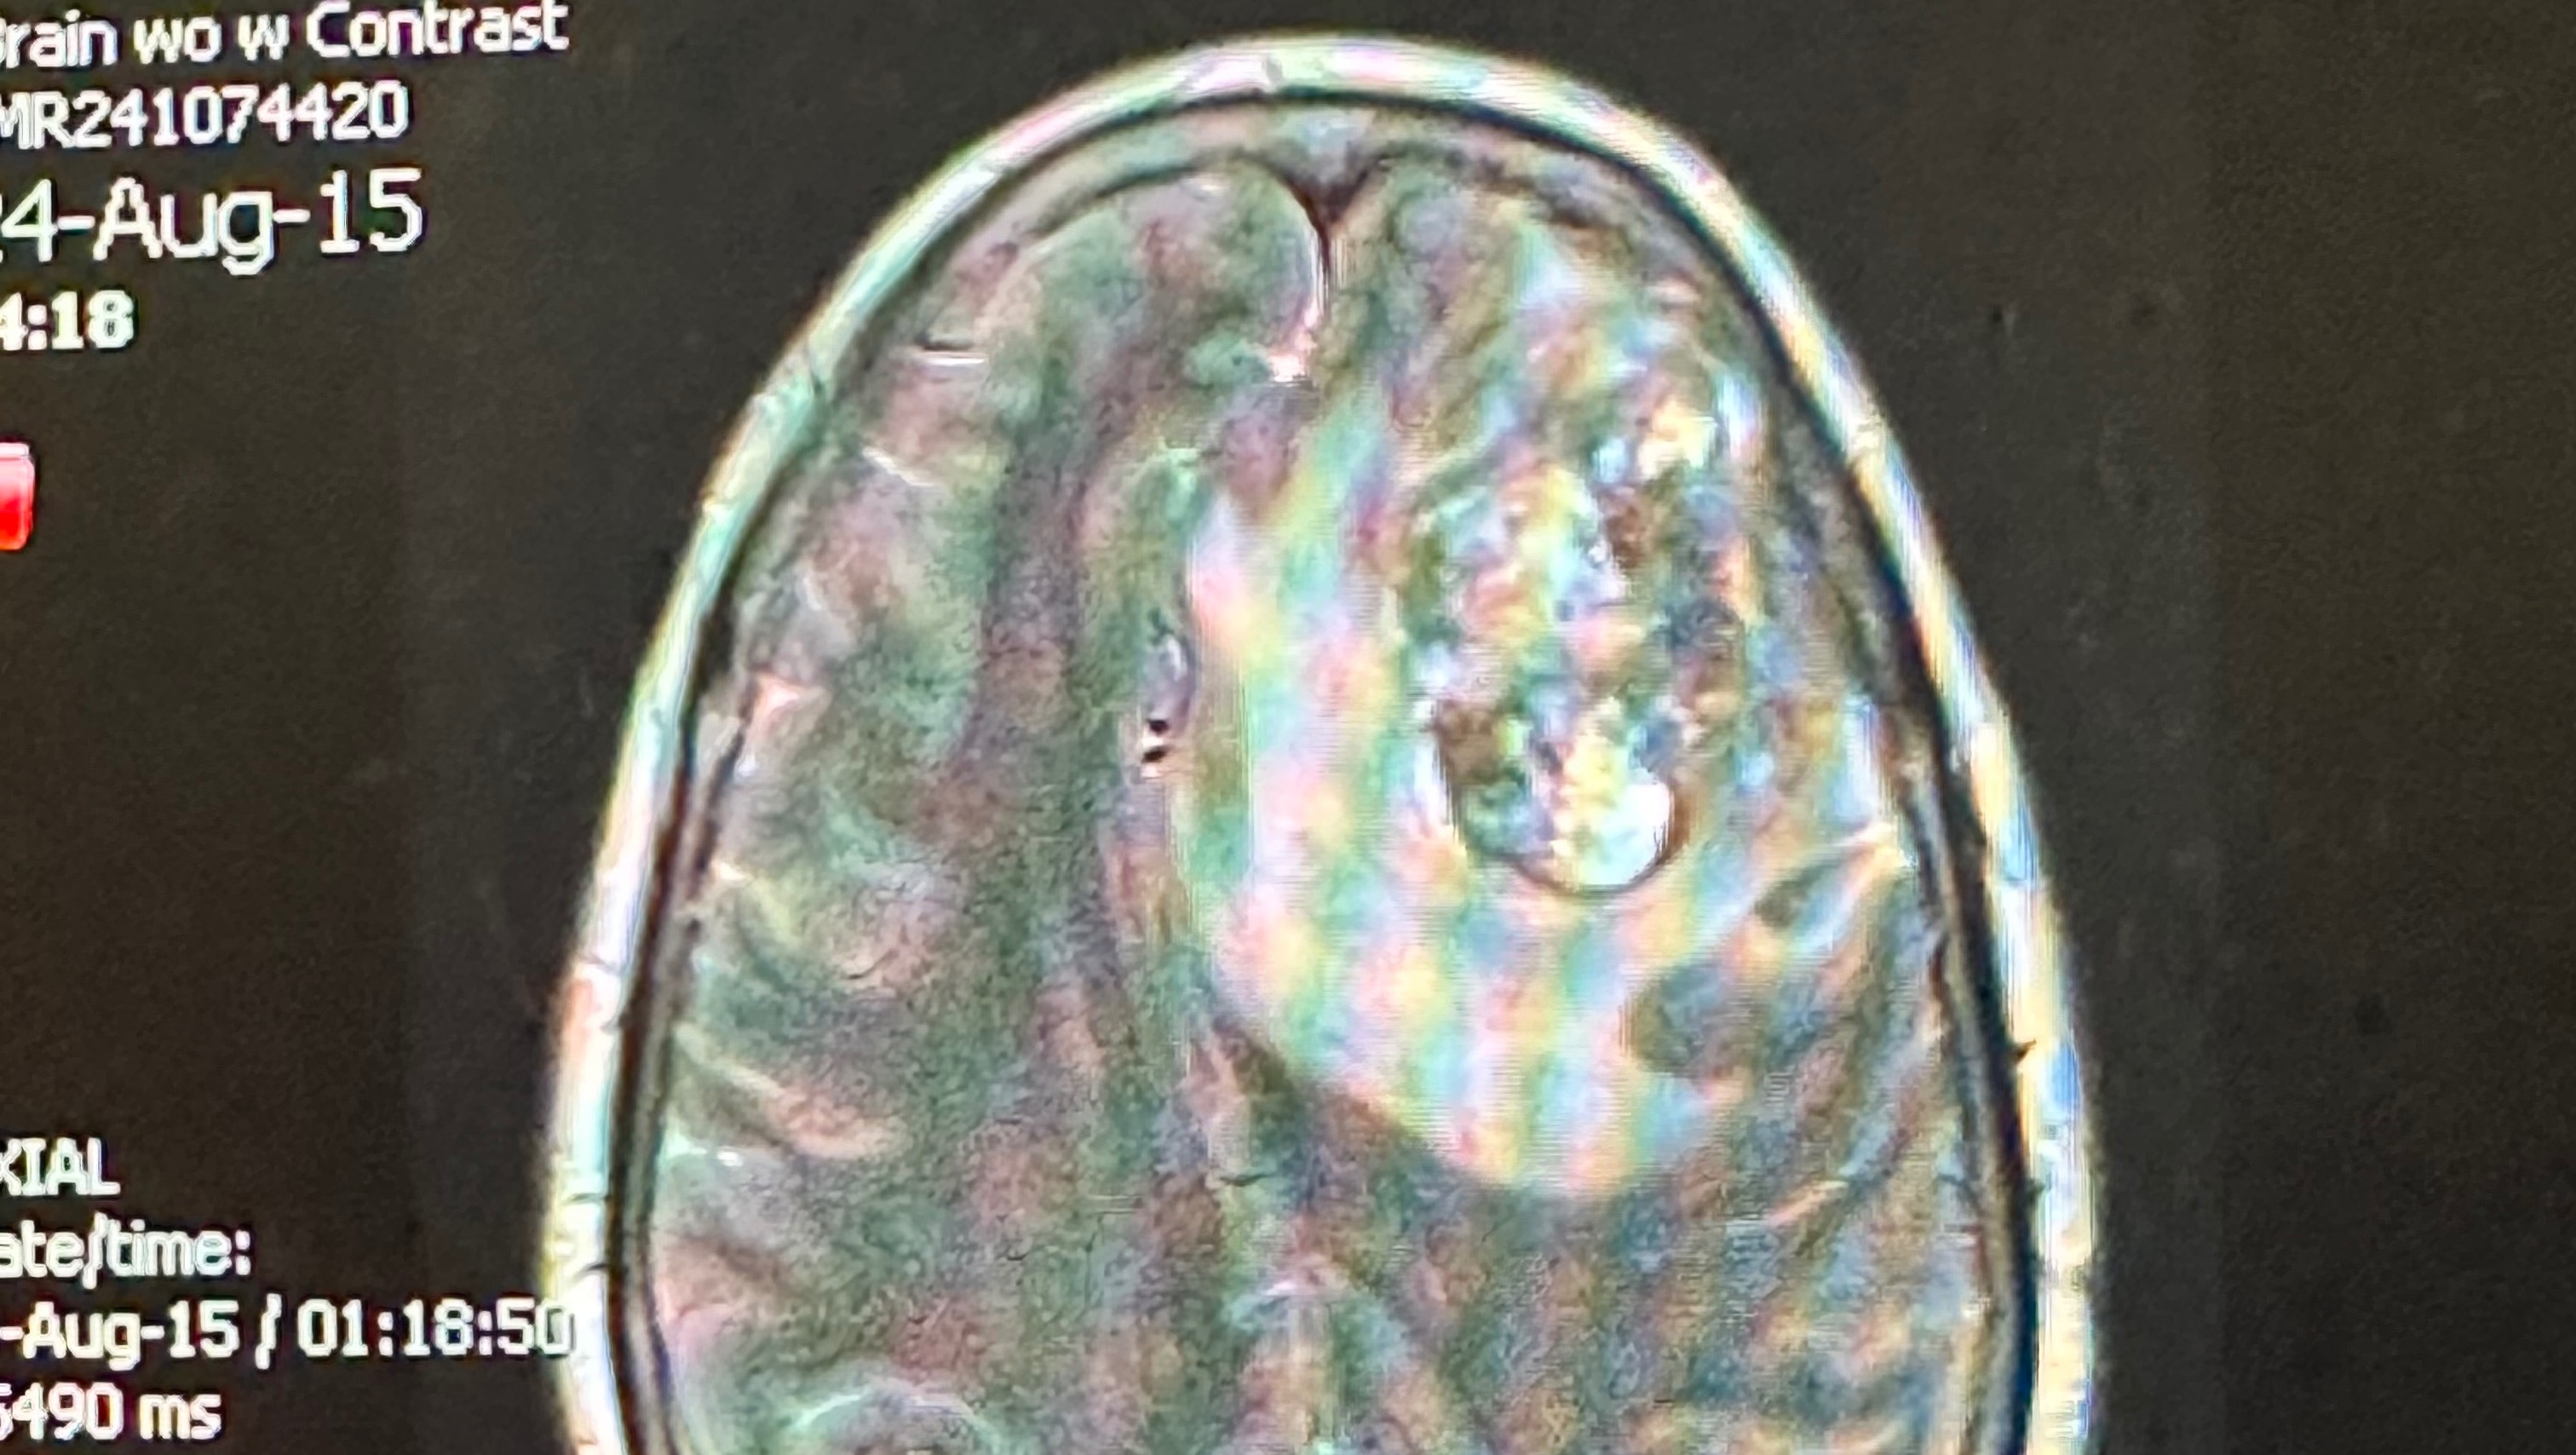

Our beloved Viola, also known as Cissy, recently endured a life-changing event. On August 12, 2024, she was involved in a car accident that led to a series of unforeseen and heartbreaking discoveries. The following day she went to Medstar St. Mary’s Hospital, for just a head injury and stitches. They ordered an MRI and CT scans to be done and revealed a cancerous brain tumor and lung cancer. Cissy was airlifted to Georgetown University Hospital, where she underwent emergency surgery to remove the brain tumor.